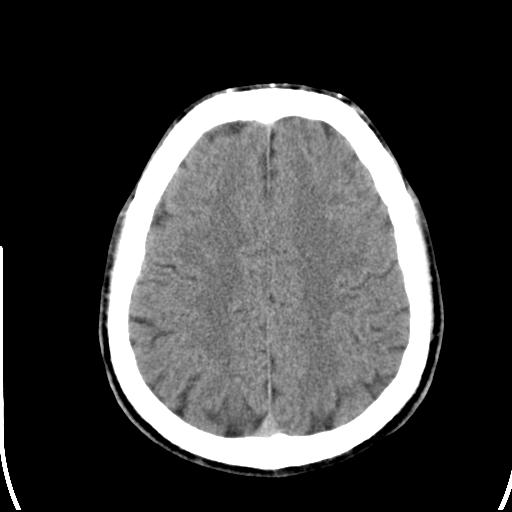

头皮下高密度结节影???临床上在老年男性比较常见。大家看看是什么?成因是? 本例患者,男性,51岁。外伤来诊。无染发史及发根植入史。

你说的是皮肤上的高密度占性影吧,没见过,不过我想一是没事,二是怎么来的可能是有点不全钙化的意思吧,没见过所以不知道

这种东西有时要结合触诊和望诊。